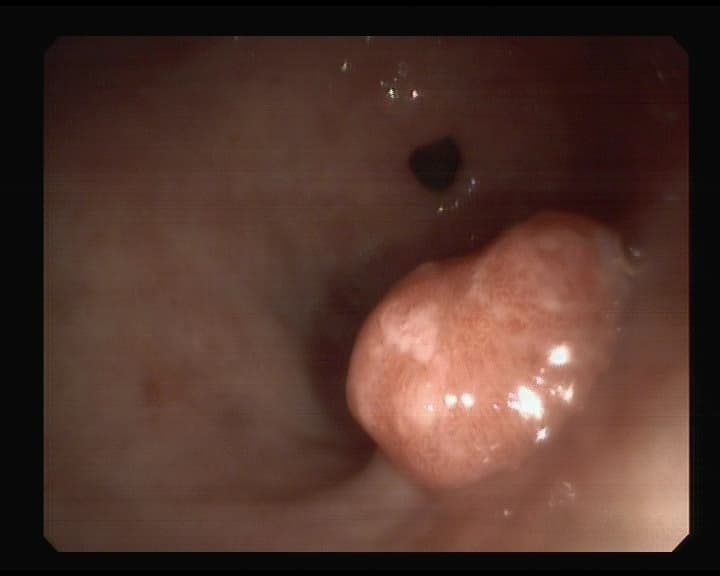

Pólipo con pedículo grueso y largo en Sigma.

Este si, es posible que sea benigno, pero si no es maligno lo hubiera sido con el tiempo. Resultó Adonomatoso en examen del patólogo, que si es el estadío previo al cáncer. Así pues se resecó y se curó de un futuro cáncer de colon.